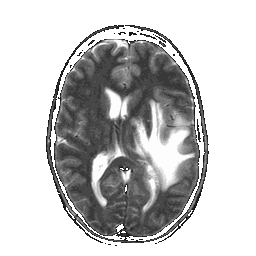

De ziekte van Creutzfeldt-Jakob

Mensen die te maken krijgen met de ziekte van Creutzfel...